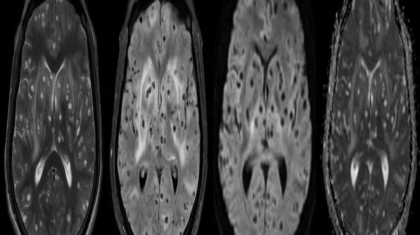

45 year old man

K/C/O Type II DM/Hypertension

Presented with bifrontal headache associated with vomiting

Visual hallucinations

Imbalance while walking

Patient developed multiple episodes of seizures, became aggressive and restless during the hospital stay